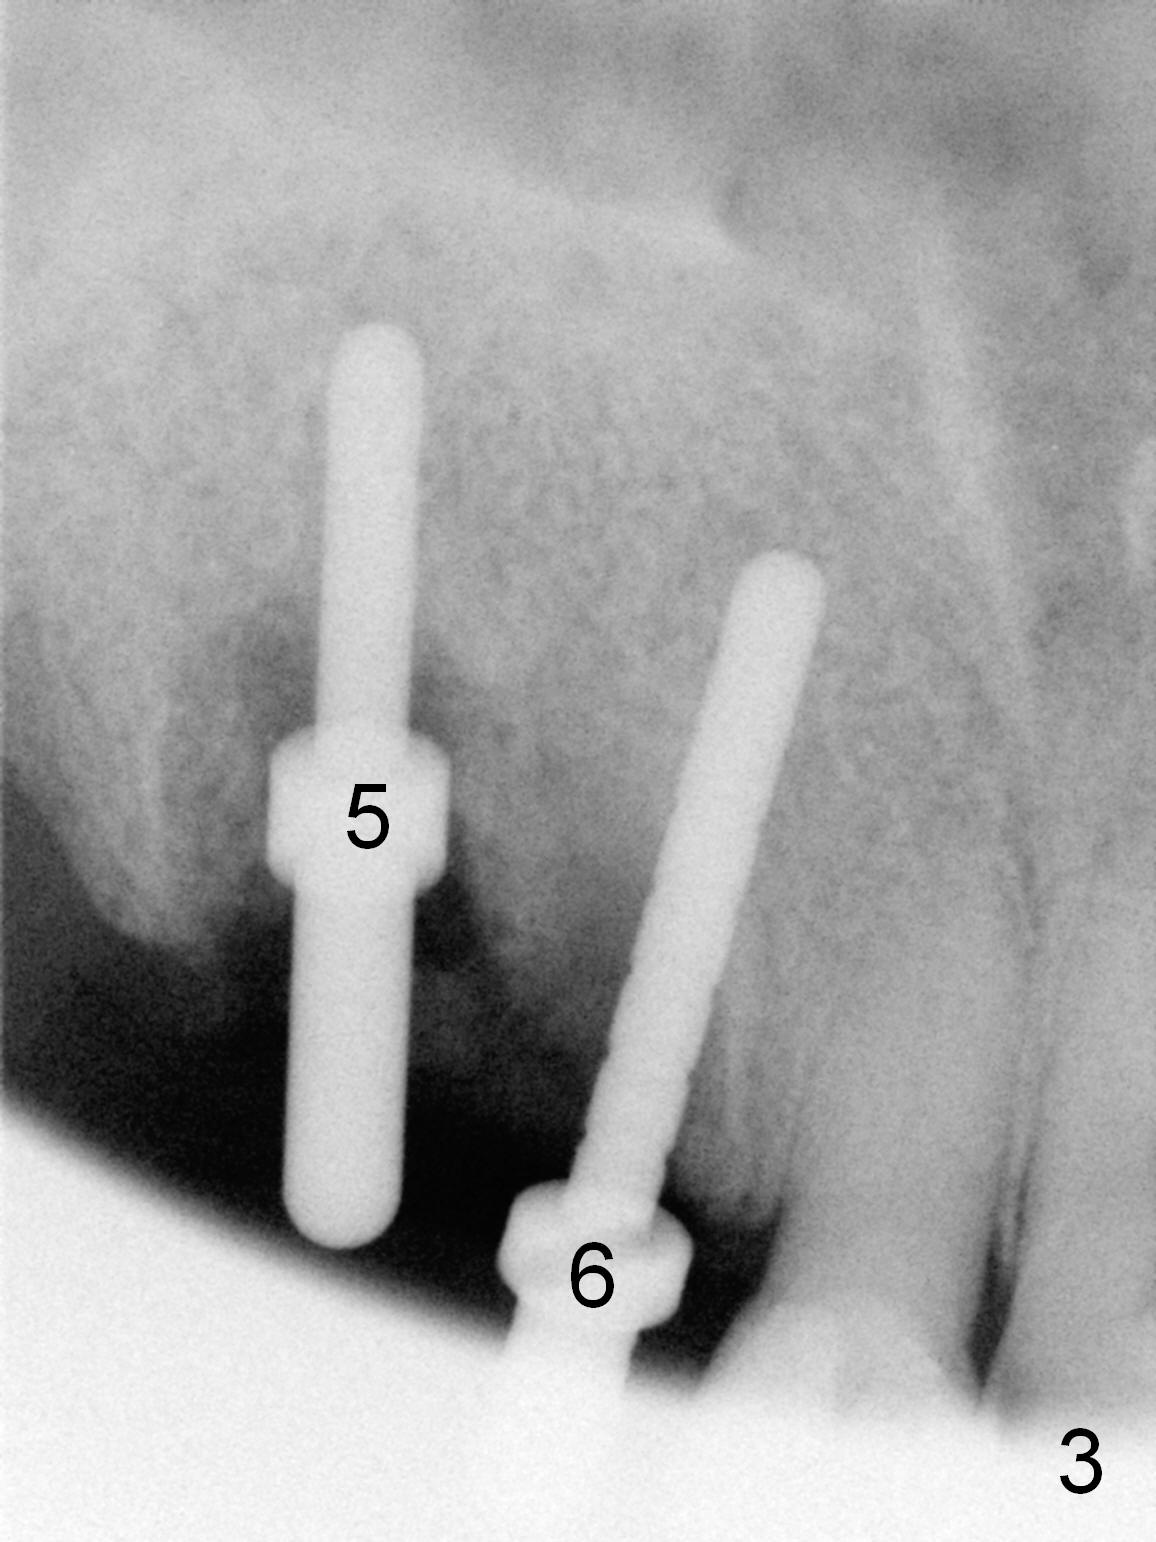

Several of CK's upper teeth (apparently in cross bite) are to be restored with implants (Fig.1).  The first two are #5 and 6; note the oval roots (Fig.2).  After extraction, and curettage, osteotomy starts in the palatal aspect of each socket.  The 1st intraop PA shows that the trajectory at #6 is incorrect (Fig.3).  After adjustment, osteotomies look parallel (Fig.4: D: 3.5x20 mm drill; T: 4.5x20 mm tap).  This suggests how important it is to use parallel pins to check initial osteotomies for neighboring implants (Fig.3).  The trajectory of the implants remains acceptable (Fig.5: 4.5x20 mm with insertion torque »60 Ncm); so is the position of the implants (as palatal as possible; Fig.6 (*: bone graft)).   Immediate provisionals are fabricated in cross bite.